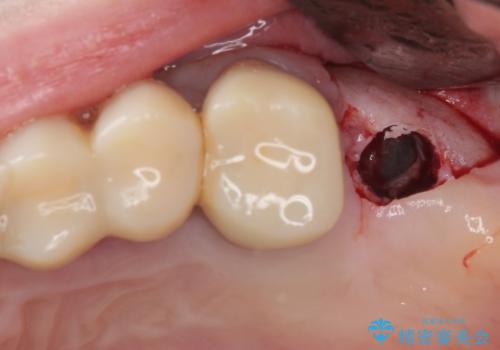

かかりつけ医では、歯周病治療は終了したため、抜歯を行った右上奥歯にインプラント埋入を行うとの案内があったそうです。

検査を行ったところ、歯周外科処置や抜歯が必要と思われる箇所が散見されたため、あらためて当院に歯周病の初期治療から行うこととしました。